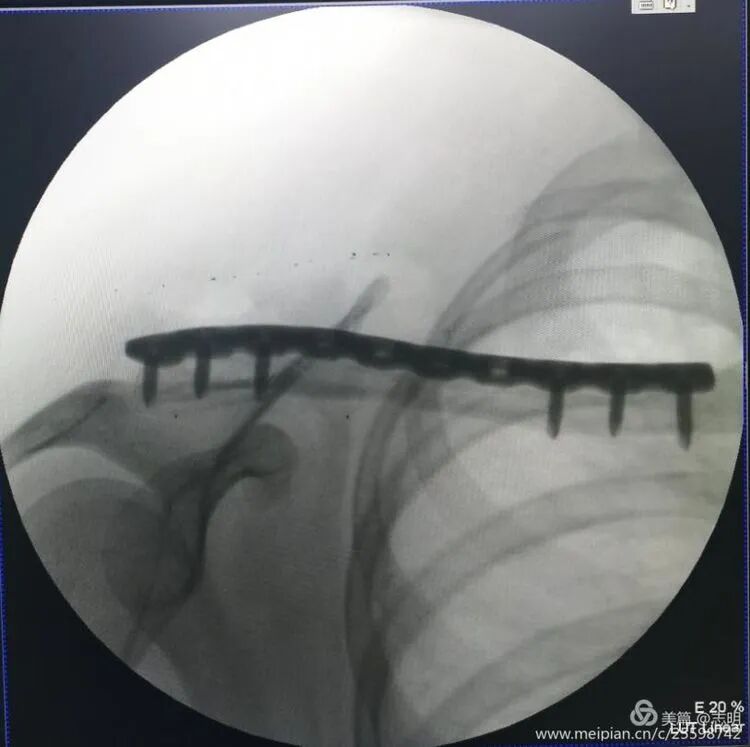

4. Plate Insertion and Fixation

-

Plate Passage:

Once reduction is satisfactory and temporarily stabilized, pass the pre-contoured locking plate through the subcutaneous tunnel. Use specialized plate manipulators to guide the plate and ensure it lies flush against the clavicle.

(Fluoroscopy confirming plate position). -

(Another fluoroscopy view of plate position).

4. Plate Insertion and Screw Fixation

Once the fracture reduction is deemed satisfactory and secured with temporary fixation, the pre-contoured locking plate is carefully passed through the previously created subcutaneous tunnel. Specialized plate manipulators and guides are used to ensure the plate lies snugly and flush against the superior or anterosuperior cortical surface of the clavicle.

(Fluoroscopic image confirming proper plate positioning). -

(Another fluoroscopic view illustrating the plate's final position).